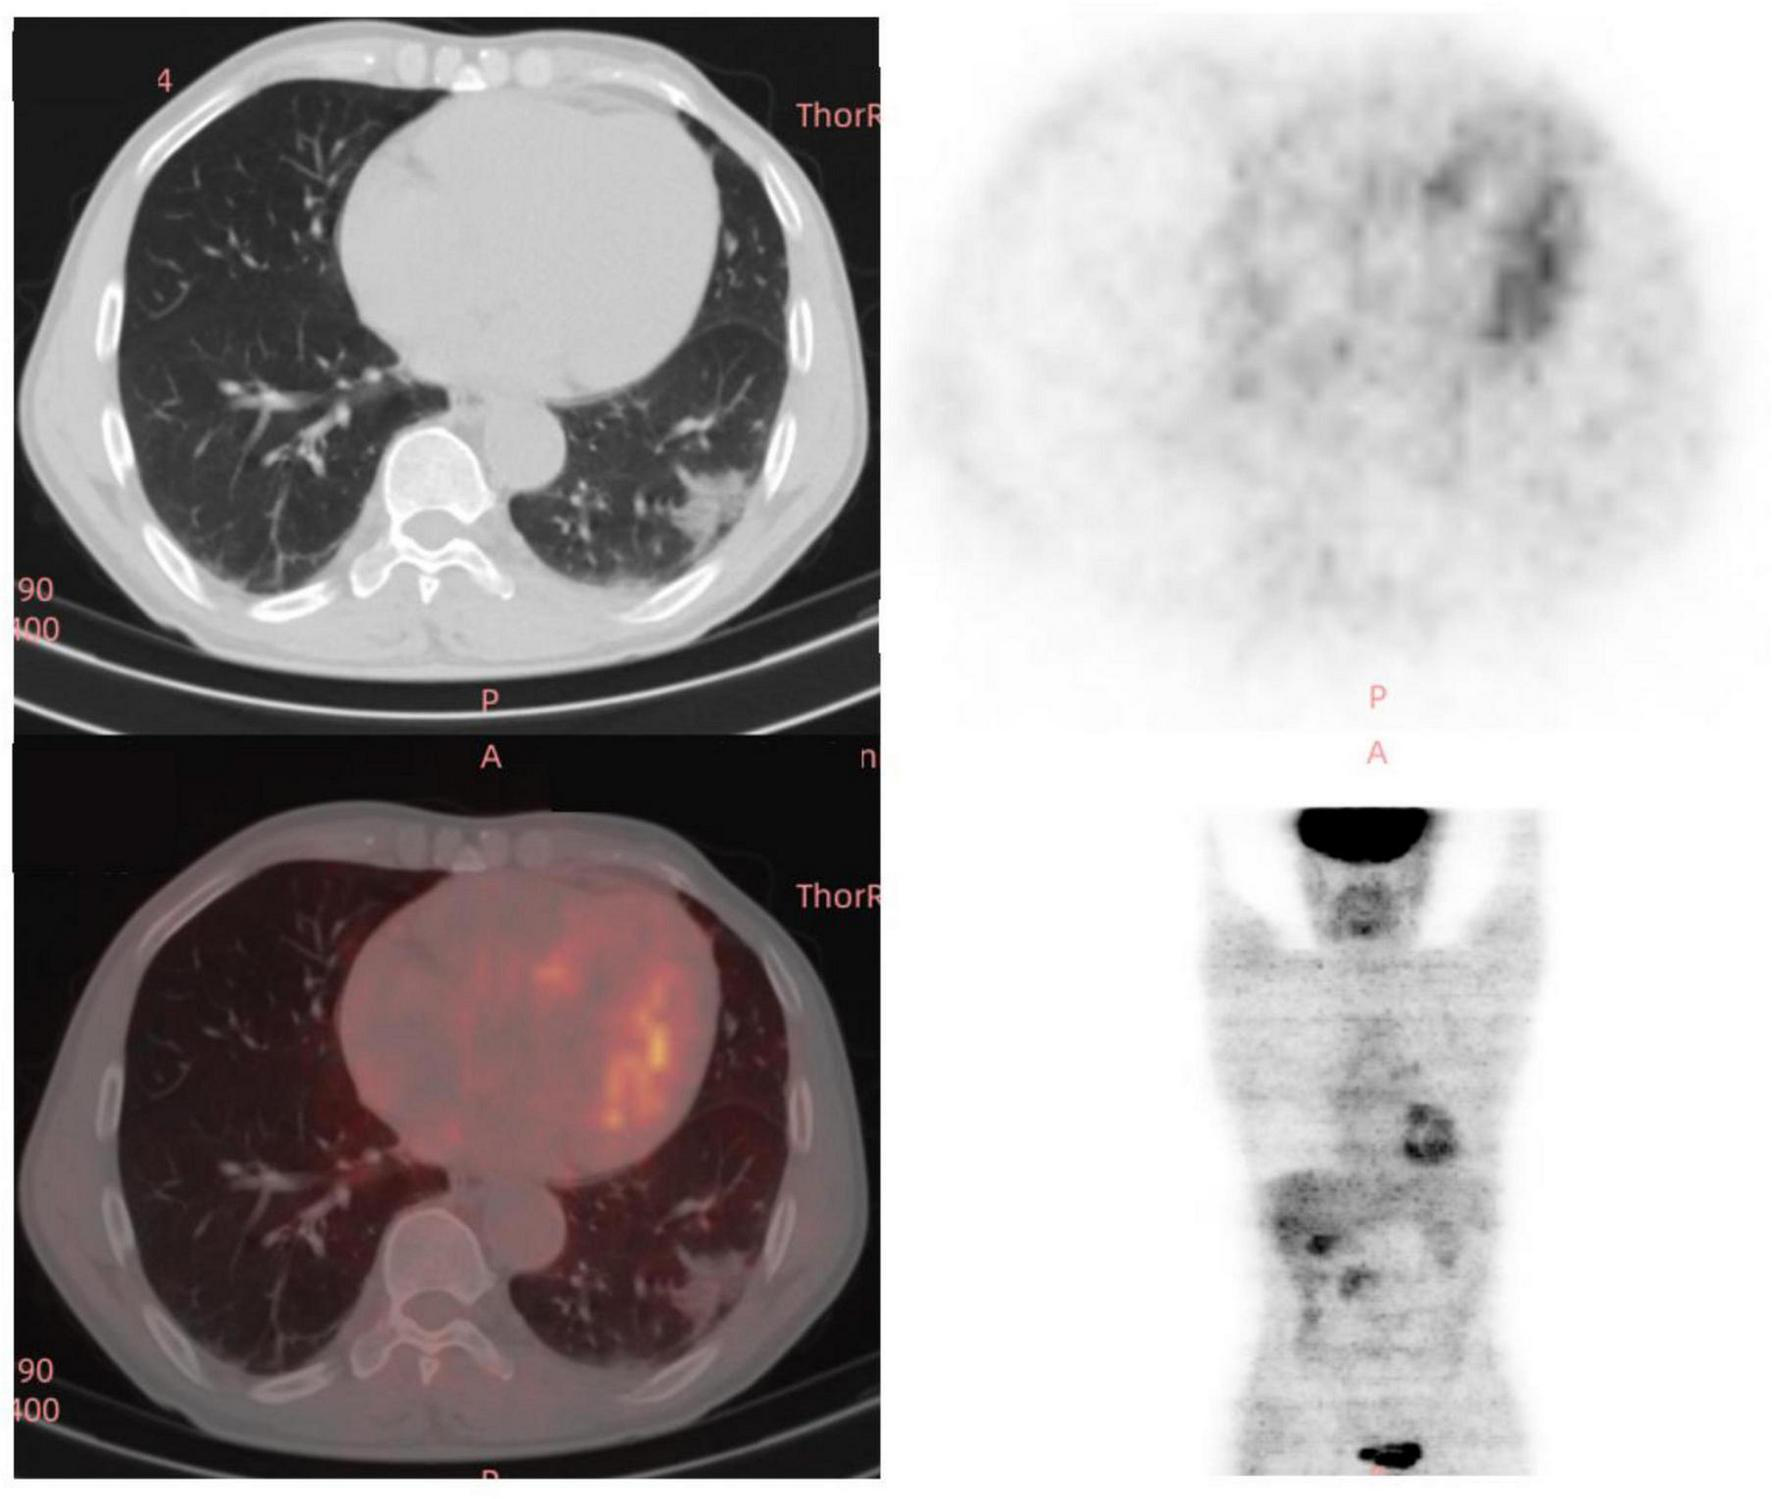

The doctors suggested that the patient undergo percutaneous lung biopsy, but the patient refused. So, the patient was recommended a CT reexamination within 1 year. In the subsequent 2 years of annual chest CT reexamination, the imaging changes of both lung lesions were still not significant (see Figure 1). These imaging features did not reveal air bronchogram, and interlobular fissure bulging. However, in the third year of re-examination, chest CT showed that the lesion in the patient’s left lung was significantly larger than before, measuring approximately 3.2 × 3.1 cm. It appears that there are blood vessels running through it, and there is a burr sign (see Figure 2). 18F-FDG PET/CT was performed to identify the nature of lung lesions (see Figure 3). From the images, we can observe that the ground-glass opacities were diffusely distributed in both lungs, especially in the lower lobes of the left lung. The FDG uptake values varied, with a standard uptake value (SUVmax) range of 6.4–24.3, while the SUVmax was 3.7. Which was greater than the SUV value of 2.5 that could be diagnosed as lung cancer. There were no obvious enlarged lymph nodes in the lung hilum or mediastinum.

FIGURE 3

A total of 18 fluoro-D-glucose positron emission tomography/computed tomography (18F-FDG-PET/CT) images of the chest in the third year (12/29/2023) of re-examination of the patient.

Imaging findings of lung IMA are critical for diagnosis and management. IMA is a rare subtype of lung adenocarcinoma characterized by distinct radiological features that could aid in differentiating it from other types of lung cancer. Common findings include solid nodules or masses, often with lobulated or spiculated margins. Lung IMA with ground-glass opacities lesion presents challenges in diagnosis (3, 6, 7). Pleural traction is also frequently observed. The imaging findings of it were mainly inferior lobe and dorsal side (gravity distribution characteristics), which easily metastasized along the spread through air spaces (STAS) and led to intrapulmonary dissemination (3). Lesions with unclear boundary of the solid or ground glass shadow, the lesions of the bronchus irregular narrow, rigid, distorted, prone to false cavity sign or vacuole sign (2). In the later stage, the lesions were often mixed in various forms, including consolidation, ground glass, multiple nodules and cystic cavity. Due to the high mucous content in the tumor, the lesion appeared as a lower density shadow than the muscle on CT, which was slightly enhanced on enhanced scan. The median maximum standardized uptake value (SUVmax) of IMA lesions is typically around 3.0, with higher values correlating with advanced disease stages and larger tumor sizes (3). In addition to CT, fluorine-18-fluorodeoxyglucose positron emission tomography (PET)/CT can provide valuable metabolic information (3). The morphologic-metabolic dissociation sign, where a malignant-appearing nodule on CT shows a low SUVmax, has been identified as a potential indicator for distinguishing IMA from invasive non-mucinous adenocarcinomas. Furthermore, thin-slice computed tomography (TSCT) has been shown to effectively classify pulmonary subsolid nodules, helping to differentiate between pre-invasive lesions, minimally invasive adenocarcinomas, and invasive adenocarcinomas (13). The morphologic-metabolic dissociation sign, based on CT and PET/CT, has been evaluated for its efficacy in distinguishing IMA from invasive non-mucinous adenocarcinomas of the lung (3).